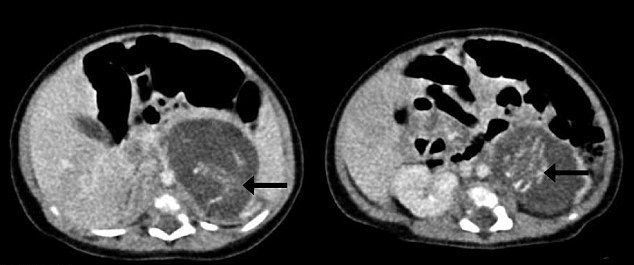

Когда новорожденной исполнилось три недели, ей сделали операцию, в ходе которой было удалено два плода весом 9,3 и 14,2 грамма и длиной в 35 и 37 миллиметров. Это примерно соответствует 10-недельной беременности. Оба плода имели пуповину, конечности, кожу, ткани мозга, грудную клетку, зачатки позвоночника и другие части тела.

Стрелками показаны зачатки позвоночника плода. © hkmj.org